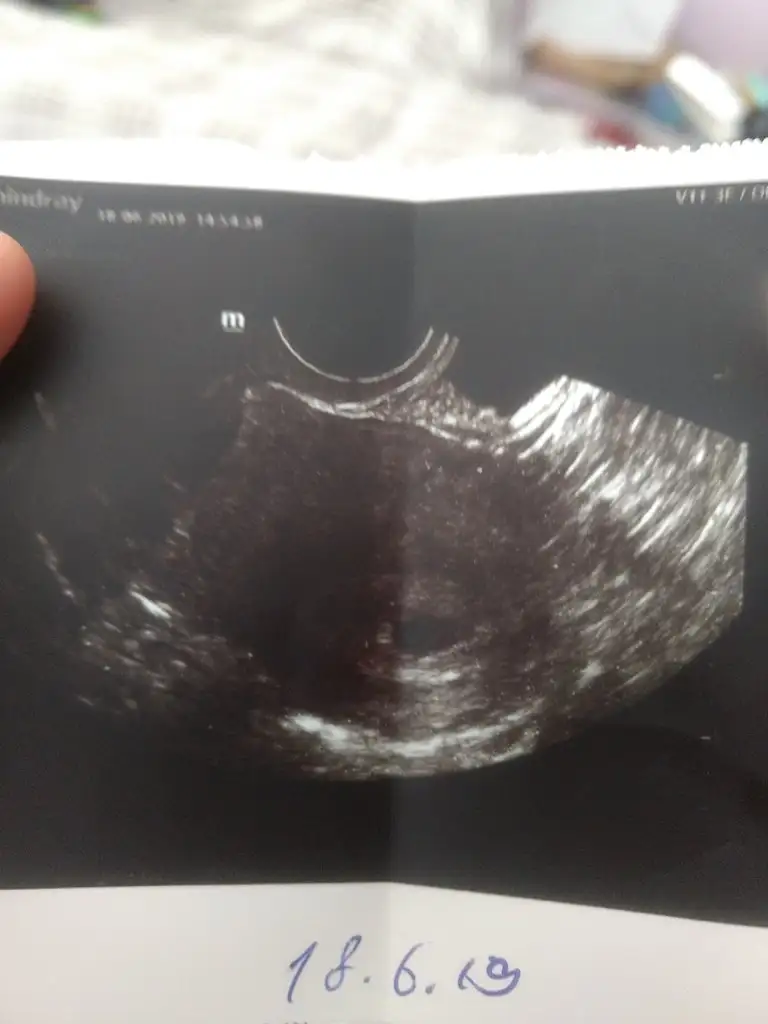

Bunu dün aldım, aslında giderken neredeyse 6 haftalık olmuştur kalbini duyabilirim diye gittim ama 4 yada 4,5 haftalık dedi doktor. Sat 11 Mayıs ve 10 Haziran'da hcg 741 çıkmıştı. Doktor üstten keseyi tam göremediği için alttan baktı ve bunu gördü sadece kalp atışını duyarız belki dedi ama kese içinde birşey görememiş çok mutsuzum şu anda. Birde ilaç kullaniyordum gyno lomexin akıntı vardı ve kaşıntı doktor fazla etki etmez ama ben olsam bunu vermezdim bebek düşünen birine dedi aklım çok karışık bel ağrısından ölüyorum. Doktora söyleyemedim bile ağrımi öyle küçük çıkınca.

Üzülme kuzum bende 5hafta 2 günlük gittim aynı bu şekilde sadece kese gördüm ve alttan aynı seninki gibi bana da kese kenarda dedi içe doğru büyümesi gerekiyor dedi...yarın doktora gidecem 6hafta 2günlük oluyor bakalım ben görebilecek miyim...bak benimde ultrason görüntün bu şekilde seninkine çok benziyor..